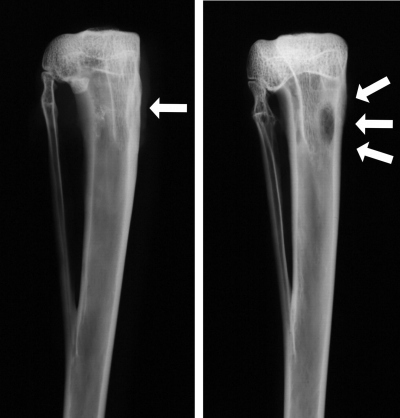

Along with the symptoms listed above, there are clinical tests to determine if osteomyelitis is present. They include blood cultures, bone biopsies, scans, x-rays, magnetic resonance imaging (MRI) and needle aspiration. If a doctor suspects that a patient may have a bone infection, it is important to order a test so that treatment may begin as soon as possible.